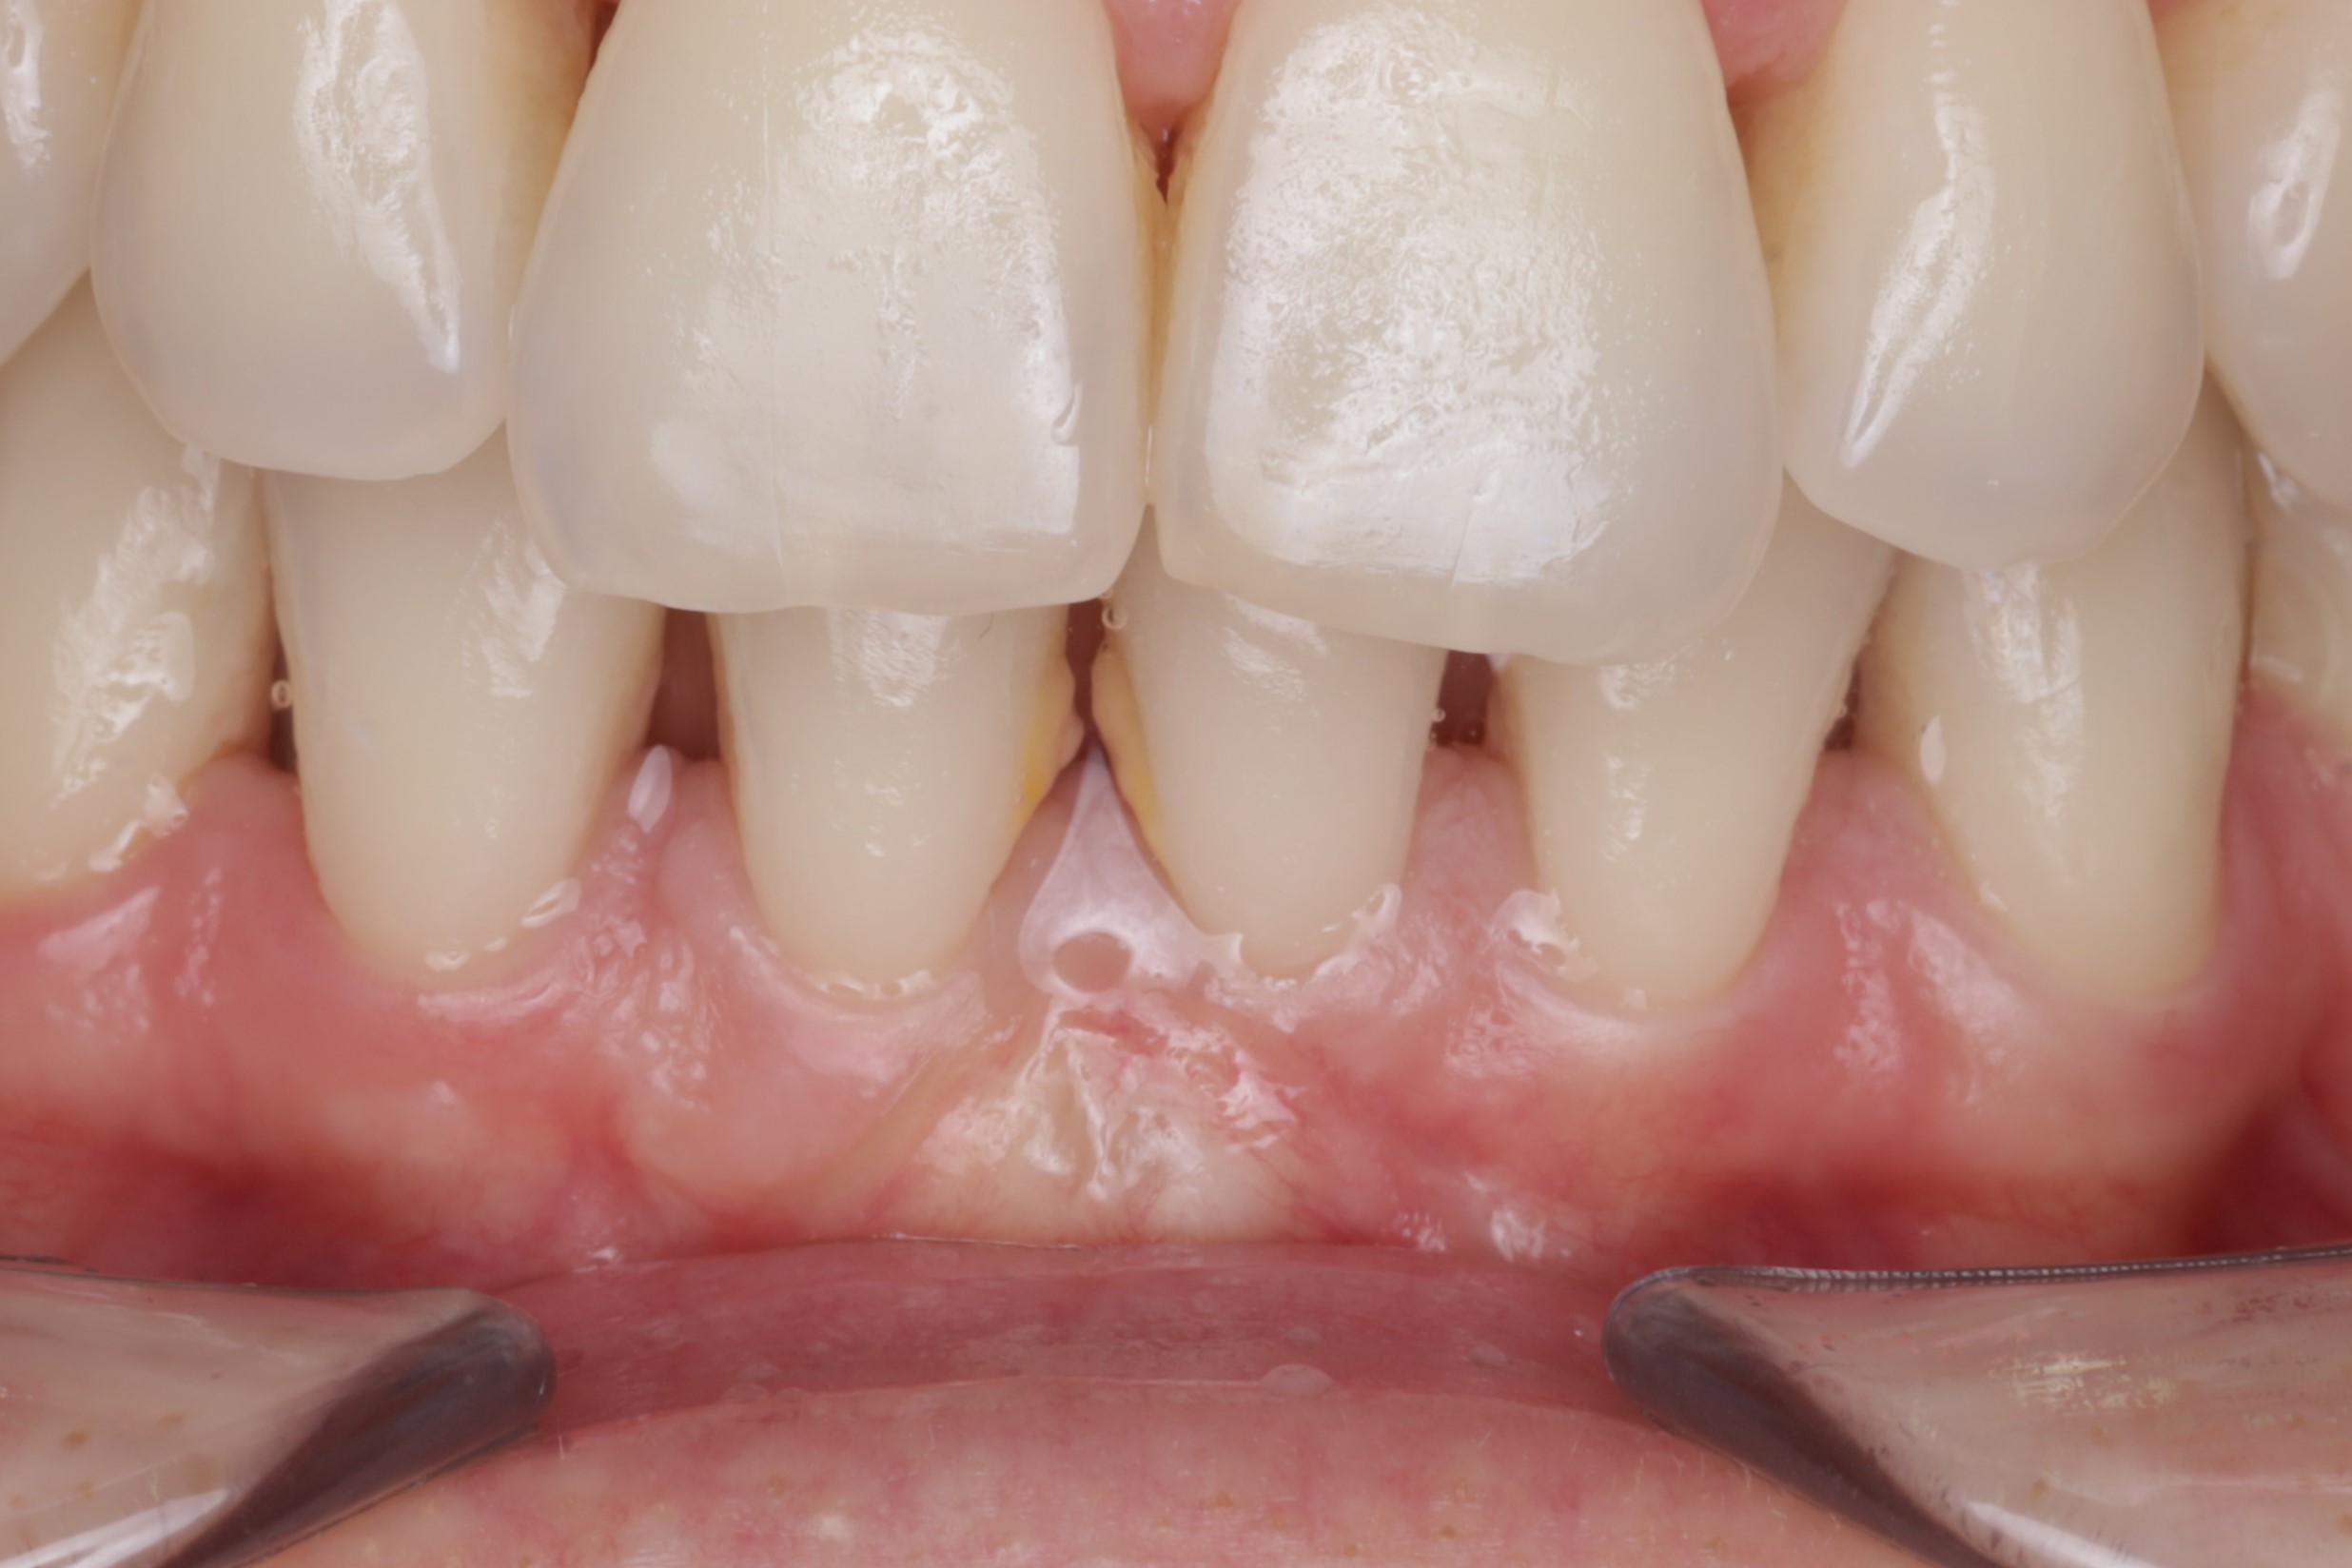

через 4 месяца после операции мы видим явное улучшение клинической картины

для наглядности полученного результат коллаж с фотографиями до и после